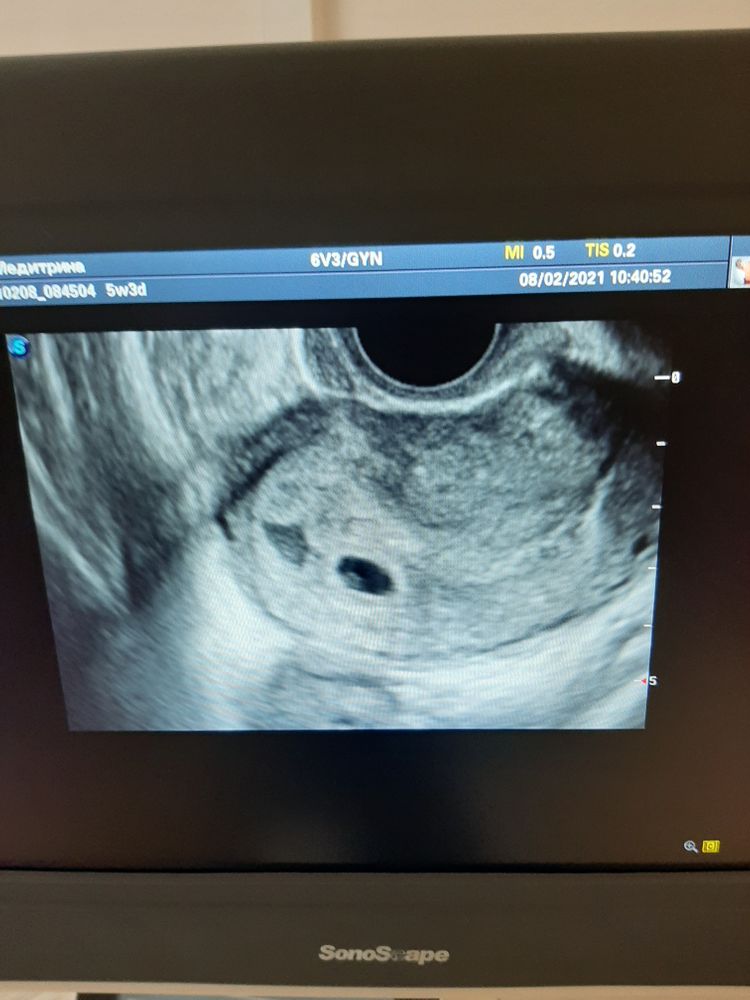

Шпаковская, плодное яйцо было 6 мм, желточный мешок 1.8мм)) хгч еще не сдавала , гениколог сказала все анализы и на учет уже вставать там куда переезжаем ,в понедельник уже едем)